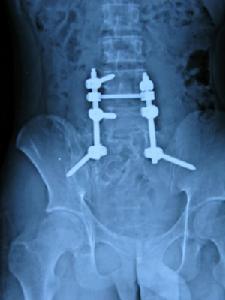

若椎體出現病理性骨折成角畸形或有神經脊髓受壓症狀宜行椎體次全切除減壓並植骨融合以維持脊柱的穩定性本病預後一般良好手術治療包括刮除刮除植骨局部大塊切除(蝶形手術)段截甚至截肢等方法。單純刮除刮除植骨復發率較高(20%~60%)個別病例可多次復發。局部大塊切除或段截方法,操作和術後處理比較複雜術後需要骨移植,這種方法治療比較徹底,復發率很低Biesecker報導8例William(1986)報導6例均無復發為了減少出血,可在術中套用止血帶或暫時阻斷大的供應動脈。對脊柱骨盆及股骨近端的病變套用選擇性血管栓塞可達到較好的效果。這種方法用於術前以減少術中出血亦可為單獨的治療方法。